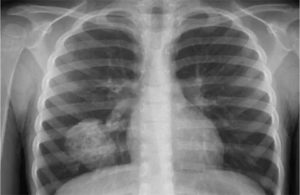

Рентген здоровых легких

Рентгенография лёгких представлена снимками в двух проекциях, на которых хорошо видны: лёгочная ткань, рёбра, ключицы, плечевой пояс, купола диафрагмы, сердечная тень и тени органов средостения, сосудистого пучка, позвоночного столба и грудины, которые накладываются друг на друга.

Для правильной расшифровки рентген-снимка важно знать: как на рентгенограмме выглядит норма. Лёгкие представляют собой воздушный орган. Даже незначительные затемнения, просветления или асимметрия лёгочного рисунка могут свидетельствовать о серьёзной патологии на ранней стадии развития.

- чёткость и контрастность рентгенограммы — определяется силой рентгеновских лучей, выбор режима «Худой», «Средний»,«Полный» делает врач. Основываясь на индивидуальных особенностях человека (при большей массе тела и выраженных жировых отложениях требуется увеличить дозу рентген-лучей для чёткого снимка), при помощи цифрового анализа возможно усиление или ослабление контрастности. Здоровые лёгкие (снимок позитив) Здоровые лёгкие (снимок негатив)